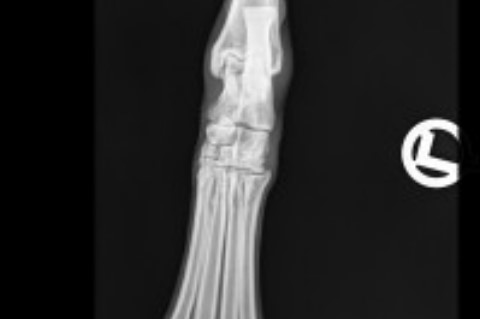

Röntgen

Ist eine bestehende Lahmheit lokalisiert, kann eine Röntgenuntersuchung sinnvoll sein, um das Ausmaß des Schadens zu ermitteln und die richtige Therapie einzuleiten. Frakturen, Luxationen und Bandabrisse sollten chirurgisch versorgt werden. Zerrungen und Prellungen benötigen meist nur Ruhe. Bei tumorverdächtigen Prozessen entscheidet das Biopsie-Ergebnis über das weitere Vorgehen.